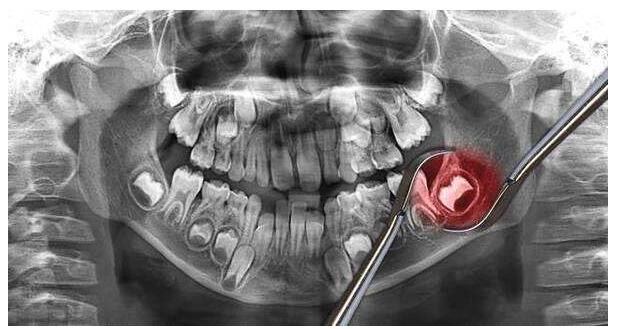

智齿拔除的实拍图

冠周炎不仅会让你身体上感到疼痛,它还会影响牙齿的健康问题,由于智齿的萌发本来就是一场牙齿排位战,阻生齿的生长,会为其他牙齿的生长带来负担,造成牙齿排列不齐的情况。并且阻生齿的生长会形成清洁盲区,日常清洁不到位,会产生其它牙齿的健康问题,进而产生龋齿。

3.若智齿生长出阻生牙,避免牙齿不齐的情况和冠周炎的反复发作,应及时看医生,及时拔除智齿。